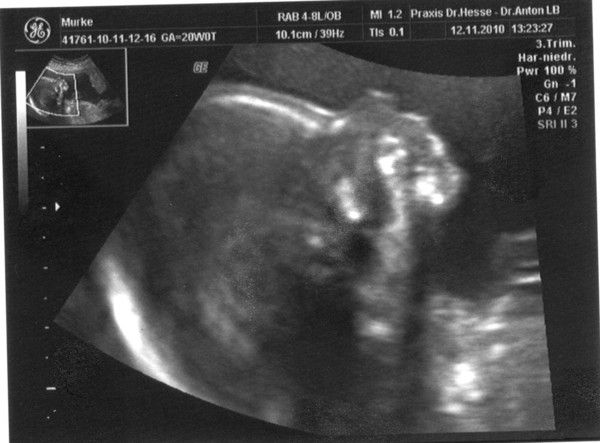

Krümel hat in SSW20+0T(21.SSW) eine Größe von 21cm erreicht und wiegt schon 280g

12.11.2010

Herzschlag war 143 bpm

So wie es aussieht ist es ein Maedchen (zu 95%)